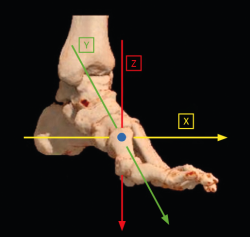

En la actualidad, el paradigma de la tridimensionalidad de la deformidad promulgado por Dayton et al. nos acerca a comprender muchos de esos interrogantes, aunque quedan muchos por resolver.

Creemos que la primera articulación tarsometatarsiana (1.ª ATMT) desempeña un papel importante en la génesis de la deformidad y es el lugar indicado para la corrección del hallux valgus cuando esté presente una rotación del primer metatarsiano (M1).